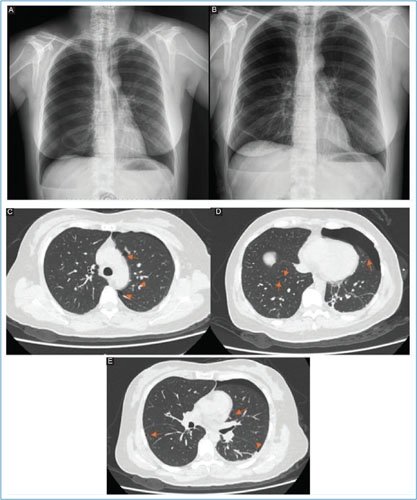

En enero de 2024 presentó un nuevo episodio de neumotórax derecho, por lo que acudió a una unidad privada donde se le colocó un catéter pleural de bajo calibre y se le realizó pleurodesis química sin complicaciones, con resolución del cuadro. Sin embargo, 3 meses después presentó un tercer neumotórax derecho, motivo por el cual acudió a nuestra unidad. Se manejó de nuevo con catéter pleural de bajo calibre, logrando la resolución en 48 horas (Fig. 1A). La paciente solicitó el alta voluntaria tras la resolución del cuadro; sin embargo, 13 días después presentó un nuevo neumotórax derecho (Fig. 1B). Ante la recurrencia, se decidió intervención con catéter pleural de bajo calibre para resolver el neumotórax y hospitalizar a la paciente con el objetivo de realizar un abordaje diagnóstico ante la sospecha de probable linfangioleiomiomatosis. Se inició tratamiento empírico con sirolimus a dosis de 1 mg cada 24 horas por vía oral y budesónida/formoterol 160/4.5 µg en inhalador (1 inhalación cada 12 horas). Cuatro días después de su ingreso presentó un nuevo neumotórax derecho. Se solicitó tomografía computarizada pulmonar simple, en la cual se evidenció la presencia de aproximadamente 15 formaciones quísticas a diferentes niveles (Fig. 1C a E). Los estudios de laboratorio no mostraron alteraciones relevantes para el caso (Tabla 1).

Figura 1. A: se observa neumotórax espontaneo derecho B: se destaca expansión pulmonar derecha con catéter por válvula de Heimlich C: se destacan presencia de múltiples bullas pulmonares D: presencia de neumotórax izquierdo con múltiples bullas en ambos pulmones E: presencia de bullas a nivel basal pulmonar bilateral.